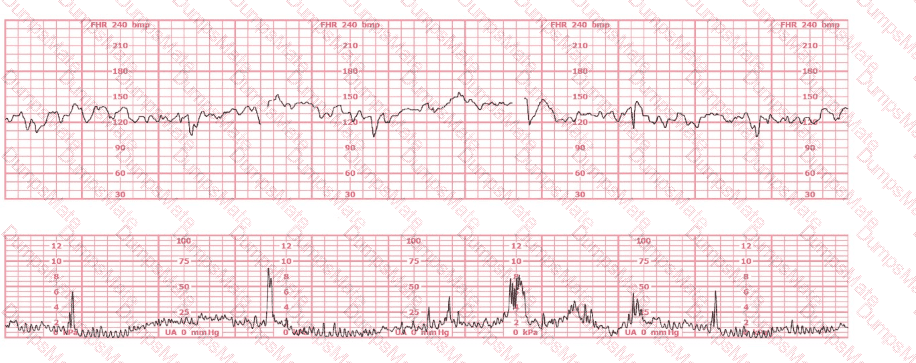

This is a fetal heart rate tracing of a multiparous woman whose cervix is 7 cm dilated on admission. The most likely cause for this pattern is:

EFM Question 20